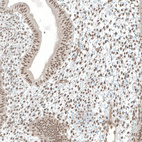

Immunohistochemical staining of human endometrium shows moderate nuclear positivity.